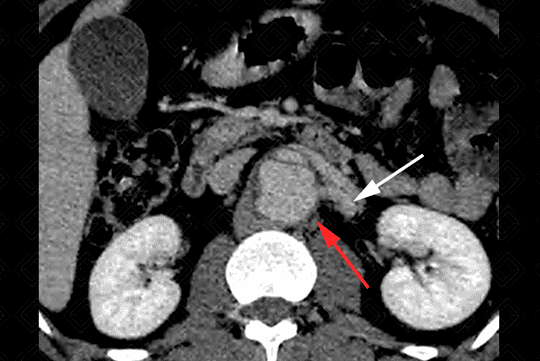

Descrição das imagens: Extensa dissecção da aorta descendente com dilatação da luz falsa (setas vermelhas) e redução das dimensões da luz verdadeira (asteriscos). É importante detalhar o suprimento dos ramos aórticos, ou seja, se estão sendo supridas pela falsa ou verdadeira luz. Neste paciente, observamos que a artéria renal esquerda (seta branca) está sendo suprida pela falsa luz (seta vermelha).

• Figura 3: Definir origem dos ramos aórticos;